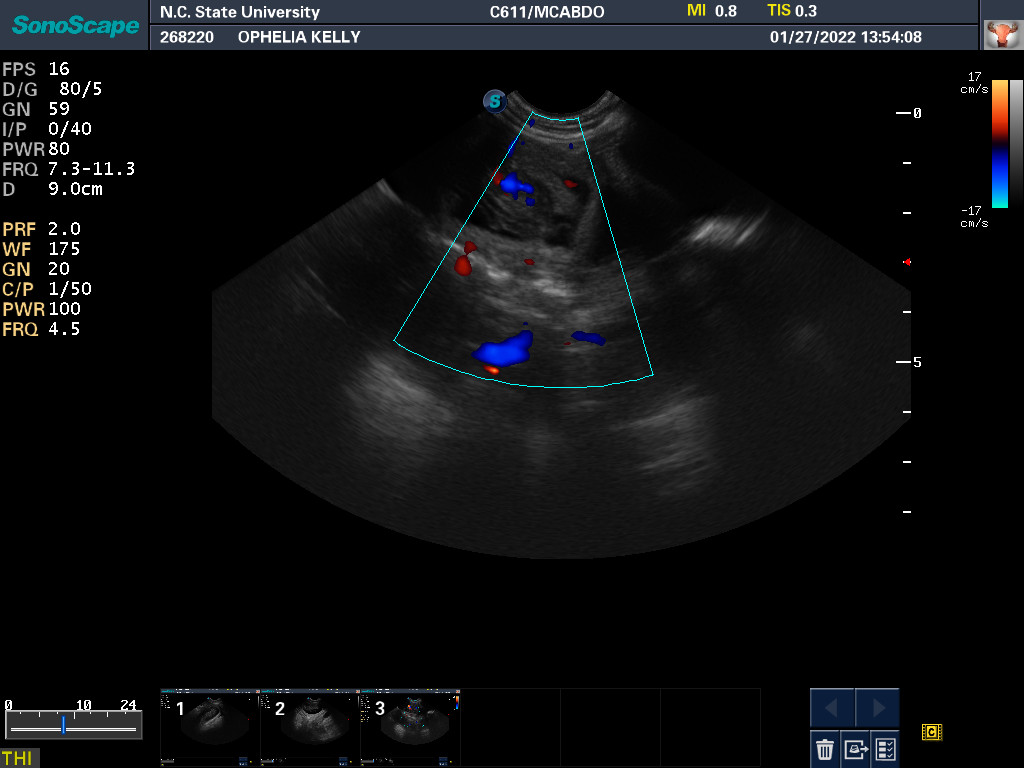

27 Jan 2022

Ultrasound today by the theriogenology (reproduction) veterinarians at NC State University showed that Ophelia is pregnant with three puppies, possibly four puppies. (It can be difficult to accurately count puppies using ultrasound.)

The x-ray also revealed that it is unlikely that Ophelia will be able to free-whelp the puppies. The size of the skulls of the puppies is larger than Ophelia's pelvic opening. This is called fetal-pelvic misproportion (or more technically cephalopelvic disproportion), and in my opinion is the reason many Norwich have difficulty free-whelping. So we are planning on a c-section for Ophelia. From now until the c-section, every morning I will be taking Ophelia to NC State, where my repro vets will test her progesterone level and check the status of the puppies via ultrasound. When the puppies are sufficiently "cooked" (developed), they will do a c-section. Most likely this will be Thursday based upon when Ophelia ovulated.

22 Feb

This morning I took Ophelia to NC State. Yesterday Ophelia's progesterone was around 8 ng/mL. Today it is around 4 ng/mL. So no puppies today. What my repro vets want to see is around 2 ng/mL. They also ultrasounded the puppies looking for GI movement and checking their heartbeats. On the way home I stopped at a grocery store and stocked up on cottage cheese and plain whole yogurt, which will be necessary when the puppies come.